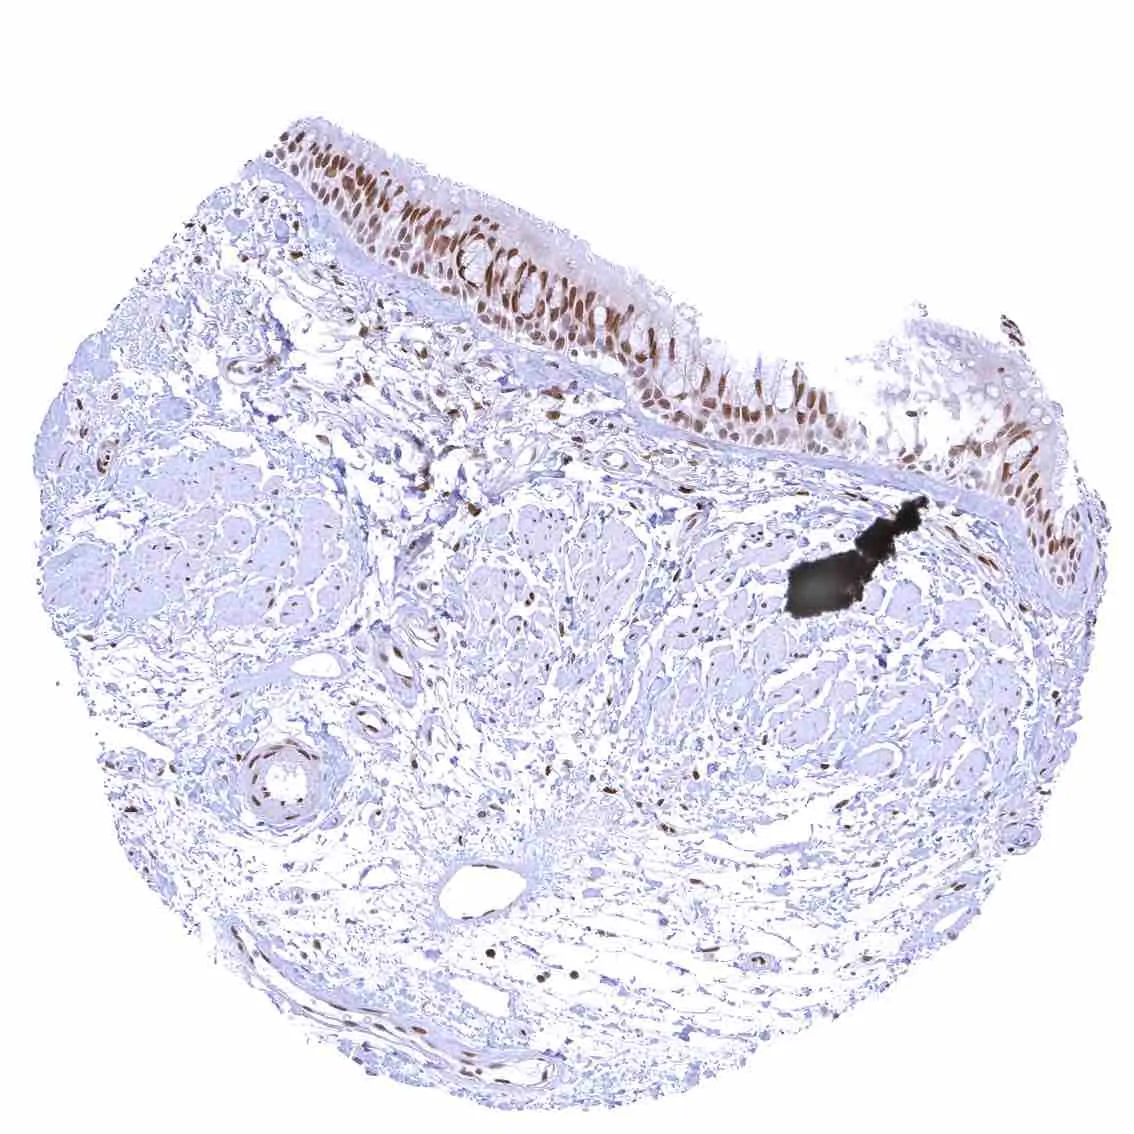

Esophagus, squamous epithelium – Nuclear staining of squamous epithelial cells predominates in the more mature cell layers (top 50_ of the epidermis).